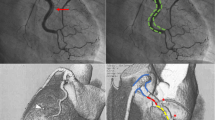

The presence of radiolucent lumens and contrast staining in the extraluminal space is descriptive of lesions suggestive of SCAD. However, in a case series described by Saw et al., only 30% of SCAD cases had this classic appearance on coronary angiography [10]. Based on coronary angiography alone, 4 major types of SCAD have been described (Fig. 2) [16].

Angiographic classification of SCAD. Type 1 spontaneous coronary artery dissection (a), type 2A spontaneous coronary artery dissection (b), type 2B spontaneous coronary artery dissection (c), type 3 spontaneous coronary artery dissection (d), type 4 spontaneous coronary artery dissection (e), and intermediate type 1/2 spontaneous coronary artery dissection (f)

Type 2 SCAD appears to be the most common, in occurring in up to two-thirds of all cases, followed by type 1 (29.1%) with type 3 being the rarest (3.5%) [10]. As previously mentioned, multi-vessel involvement has been reported to occur in 5–13% of cases.